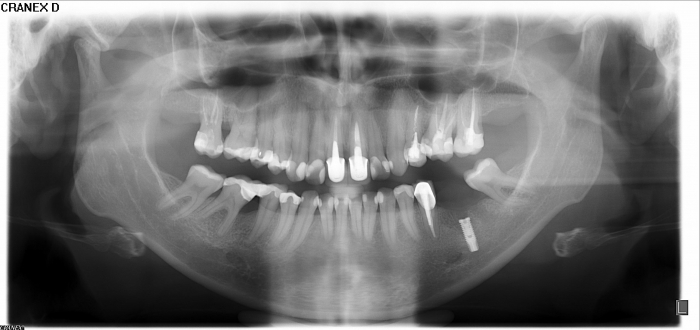

Raio X final com prótese definitiva em porcelana instalada